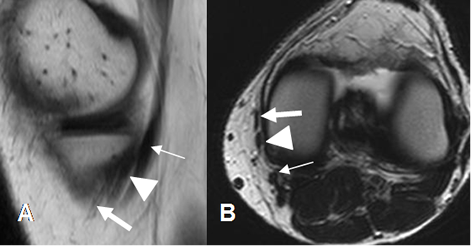

Fig 19. Ligamentos meniscofemorales normales.

A: RM coronal en T1 y B: RM coronal en STIR. Ligamento menisco femoral posterior (Flecha delgada), en relación con el LCP (Flecha gruesa). Menisco externo (Punta de flecha).